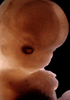

Carnegie Stage 22 (54 post-ovulatory days)

Most embryos at stage 22 are approximately 54 postovulatory days old and measure 25-27 mm in length. Distinguishing criteria for this stage include clear formation of the external ear, the hands begin to extend ventrally beyond the body wall, the fingers of one hand may overlap the fingers of the opposite hand, thickened eyelids just begin to cover the outer margins of the eye, and the superficial vascular plexus of the head now extends about three-quarters of the way above the eye-ear level.